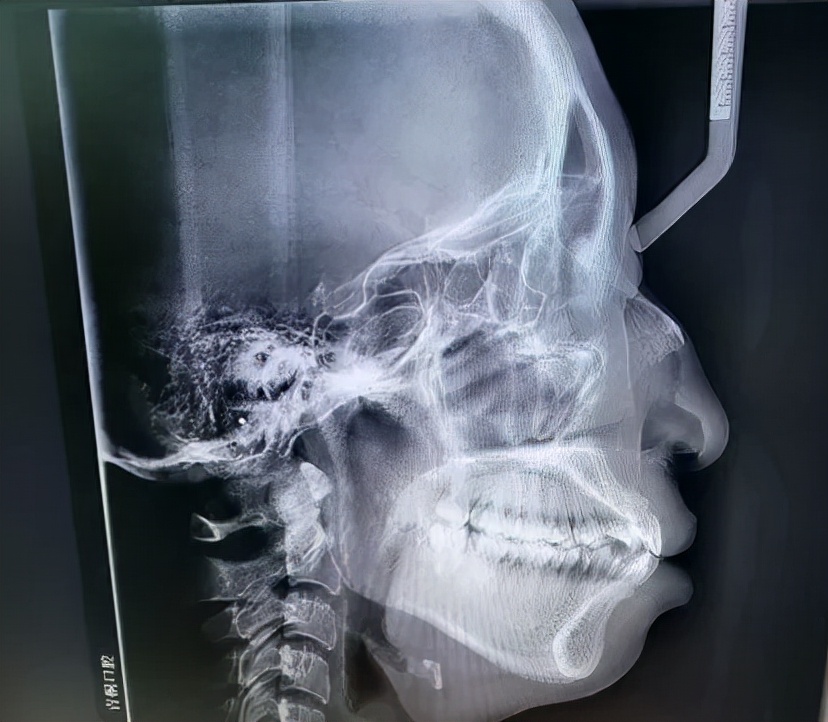

我的x光片,牙齿的和整个侧面.

需要根据实际的牙齿情况以及头颅侧位片来定夺,这张片子就是牙性骨性